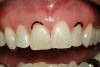

Figure 10  Facial view of the gingival tissues 9 weeks after open-flap surgery and at the time of placement of the ceramic restorations (original magnification 2x). Note the symmetrical positioning of the gingival zeniths of tooth Nos. 8 and 9. The level of tissue health 9 weeks after surgery is excellent.

Figure 10

Figure 11  The all-ceramic restorations (Venus‚Ñ¢ porcelain, Heraeus Kulzer, Inc, Armonk, NY) in place at the delivery appointment. (Ceramic artistry performed by Mr. Vincent Devaud, CFC, MDT, Pasadena, CA.)

Figure 11